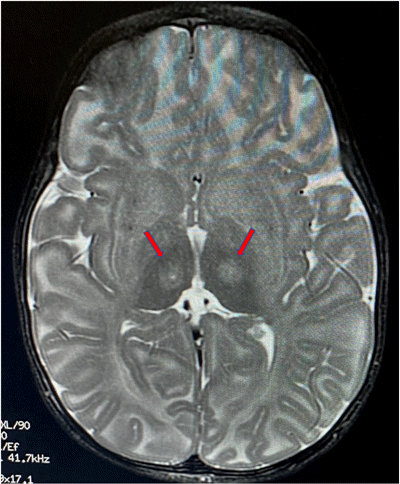

Red arrows indicate the location

in the thalamus where the

infusion is targeted.

Dr. Sena-Esteves, Heather Gray-Edwards, PhD, DVM, assistant professor of radiology at UMass Chan Medical School, and Douglas Martin, PhD, professor of anatomy, physiology and pharmacology at the Auburn University College of Veterinary Medicine, demonstrated that one shot into the thalamus would work for an entire hemisphere in animal models.